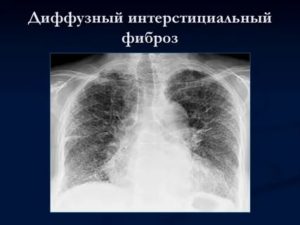

Линейная форма — появляется, как следствие осложнений после перенесенного туберкулеза, пневмонии. Интерстициальный пневмофиброз — при такой форме пациента мучает одышка, заболевание развивается вследствие воспалительных явлений в легочных кровеносных сосудах.

- Диффузный пневмофиброз легких. Самый опасный тип заболевания, который отличается полным или множественными поражениями тканей легких. При этом виде пневмофиброз развивается довольно стремительно. Появляется ярко выраженная дыхательная недостаточность.

- Диффузный пневмофиброз легких – это наиболее опасная форма заболевания, характеризующаяся множественными поражениями или изменениями всей ткани легкого. Для диффузной формы патологии характерно стремительное прогрессирование, развитие выраженной дыхательной недостаточности. В большинстве случаев состоянию сопутствует развитие плеврофиброза. Плевропневмофиброз легких – это поражение плевры, замещение ее на фиброзную ткань;